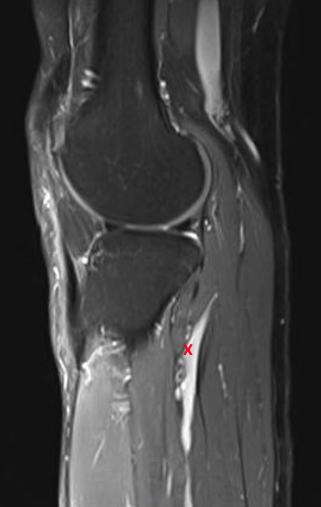

Following referral to our peripheral nerve service, patients are assessed per a standard protocol in which a comprehensive patient history is obtained and examination, including peripheral neurological examination of the lower limbs, is performed. Magnetic resonance imaging (MRI) scanning is undertaken if an intraneural ganglion is suspected. On T2-weighted imaging, a ganglion appears as a hyperintense lesion often associated with the superior tibiofibular joint (STFJ; Figure 1). Such changes as reduced anterior compartment muscle mass and secondary denervation edema may also be observed. General anesthesia without neuromuscular paralysis and intraoperative nerve stimulation is recommended for the surgical excision. Preoperatively, the patient is placed in the lateral position with the ipsilateral leg uppermost. A pneumatic thigh tourniquet may be used; however, protracted tourniquet ischemia beyond 30 minutes renders nerve stimulation thresholds unreliable due to conduction block. A curvilinear incision is made along the course of the common peroneal nerve from posterior to the biceps femoris insertion, over the peroneal nerve at the fibula neck to the junction of the septum between anterior and lateral compartments of the lower leg, with deep dissection to expose the common peroneal nerve. The common peroneal nerve is mobilized circumferentially at the level of the fibula head, and a silicone loop is passed around the nerve and used for gentle retraction. The nerve is dissected in a proximal to distal direction, releasing the fascia of the peroneus longus to expose the bifurcation of superficial and deep branches, which are each tagged with silicone loops (Figure 2). The fascia incision continues obliquely along the course of the nerve, over the anterior compartment to expose the tibialis anterior muscle. The fascial septum between the peroneus longus and the tibialis anterior is excised superficially and deep to the tibialis anterior motor branch, which is tagged with a silicone loop. The articular branch to the proximal tibiofibular joint is identified and tagged in the same way.